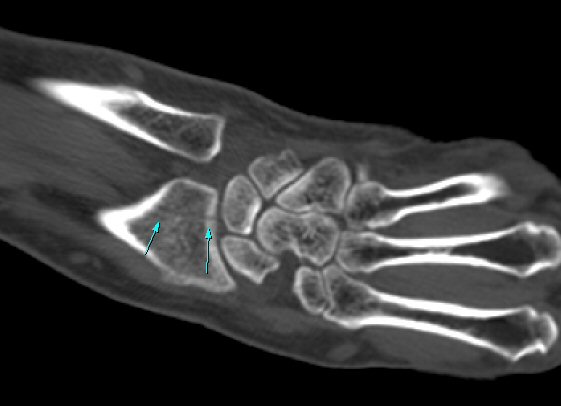

¼Õ¸ñÀÇ Á¾´Ü¸é°Ë»ç¿¡¼­ ¼Õ¸ñ °üÀý³» ºÎÁ¾ÀÌ °üÂûµÊ(»çÁø 1).